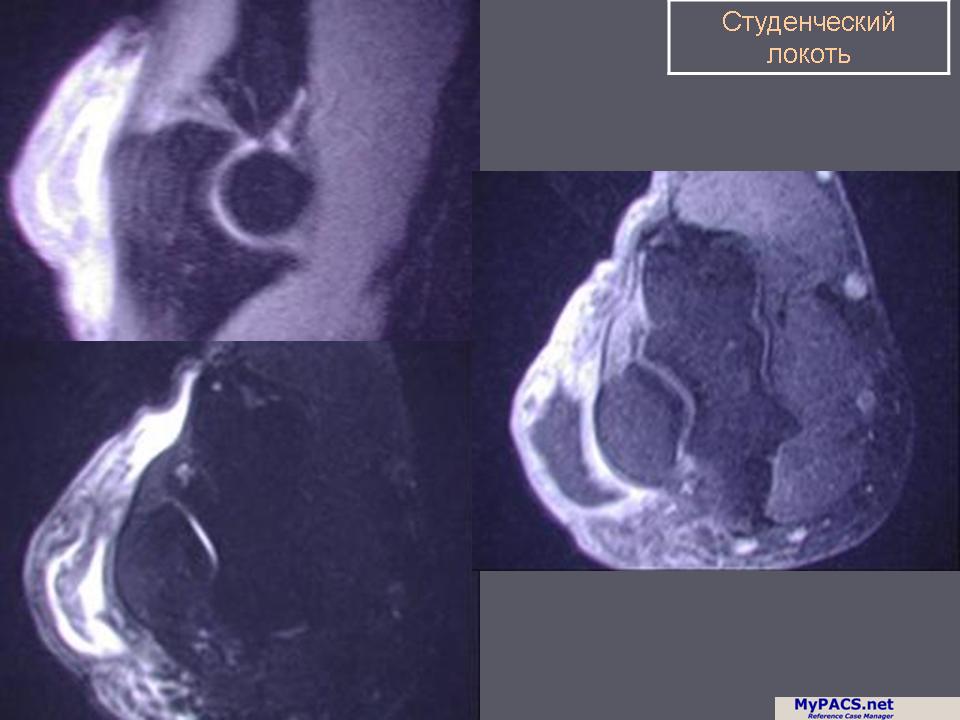

«Студенческий локоть». В основе его лежит травматический бурсит, возникающий в результате давления на локти, например, при длительном чтении захватывающей книги. Возникают боль и припухлость ниже локтевого отростка. Другими его причинами могут быть септический или подагрический бурсит [в последнем случае следует искать подагрические тофи (узлы) в других местах]. Производят аспирацию жидкости из бурсы. При травматическом бурсите в полость синовиальной сумки вводят гидрокортизон. Септический бурсит должен быть дренирован.

Бурсит локтевого отростка

Бурсит локтевого отростка - это воспаление синовиальной сумки локтевого отростка на дорсальной стороне локтя. Заболевание может быть вызвано повторяющейся механической травмой (травматический или "студенческий" бурсит). Также причиной может быть инфекция, и высказывается мнение о том, что заболевание связано с развитием подагры. В результате скопления жидкости в синовиальной сумке наблюдается местный отек и волнообразная подвижность при пальпации. При повышенной кожной температуре можно заподозрить инфекционный процесс (септический бурсит).